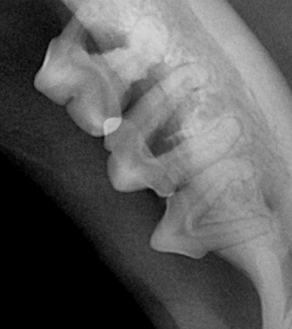

| 4기 (중증 이상) | 치아 탈락, 고름, 턱뼈 침범 가능성 | 심한 통증, 입 주변 부음, 만성 염증 |

치주염 치료는 진행 단계에 따라 다르게 접근합니다.